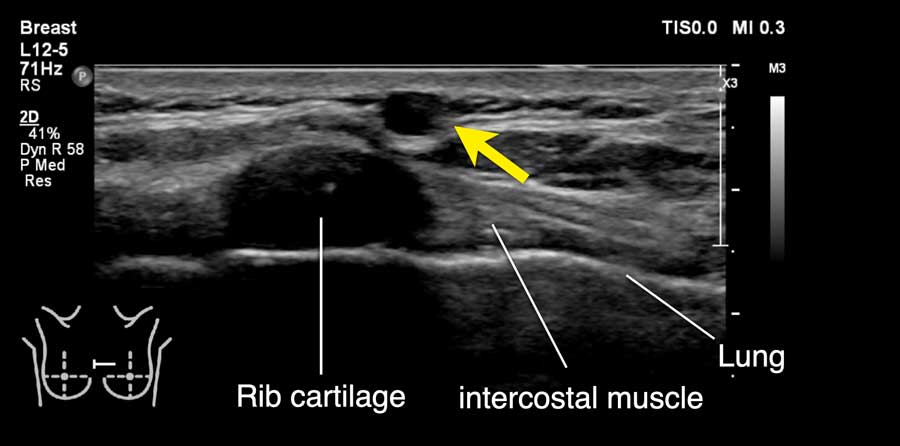

Đây là hình ảnh siêu âm bình thường của tuyến vú.

Lớp xám phía trên là da.

Tiếp theo là sự pha trộn giữa mô mỡ (tối hoặc giảm âm) và mô tuyến (xám sáng hoặc tăng âm).

Lớp có vân sọc phía sau mô vú là cơ ngực.

Phía sau hoặc sâu hơn so với xương sườn có một vùng đen hay bóng cản âm phía sau.

Phổi là lớp có thể quan sát sâu nhất.

Không khí trong phổi phản xạ hầu hết sóng âm, tạo ra một đường sáng hoặc tăng âm với bóng cản bẩn phía sau.

Gần đường giữa, các xương sườn chỉ được cấu tạo bởi sụn và chưa bị vôi hóa.

Sụn không tạo ra phản âm trắng ở mặt trước hay bóng cản âm phía sau.

Thay vào đó, một cấu trúc giảm âm được quan sát thấy phía trước phổi.

Không nên nhầm lẫn cấu trúc này với khối u vú.